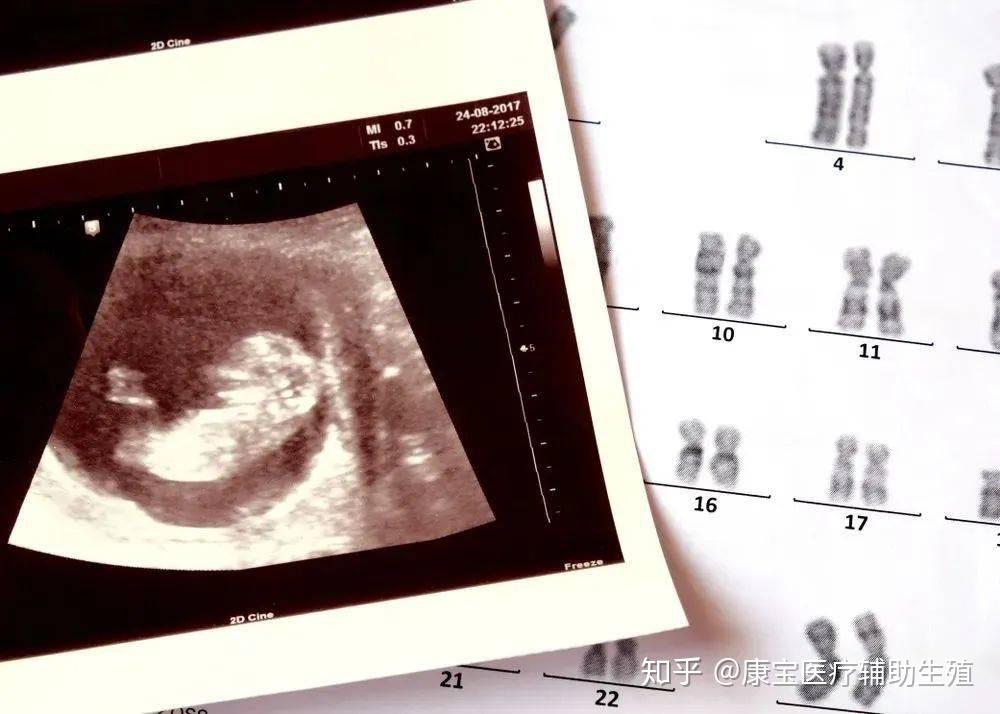

很多生育障碍的夫妇,寄希望于试管等生殖技术,来改变生活状态,但技术的不确定,让焦虑卷土重来,很多女性被身体受创与生殖焦虑反复拉扯。

“像学生查成绩一样的,医生会告诉你,现在取了多少个卵泡,培育成多少个受精卵,质量怎么样,是 A 级还是 B 级,是移植,还是直接冷冻。”曾纪琪夫妇正在尝试试管婴儿。

为了尽可能排除那一点点因素,曾纪琪和黎晓都选了更明确的方案 —— 试管。

曾纪琪决定做试管之后,开始进入各种各样的试管群和求子论坛和不同的人聊天,她看到群里有不少人经历过四五次的、甚至有十几次还没有成功的,很多人是从安徽、苏北一些县和农村来到南京租房子做试管,最低费用的一代试管,一次也需要 4~5 万,很多人举债十几万仍未成功,她想给自己打个心理上的预防针。

一关一关地过:等卵泡长到合适的时机,才到可以去取卵;取卵成功之后,要再等待卵子和精子结合成功,在这之后才能真正地进入移植期。